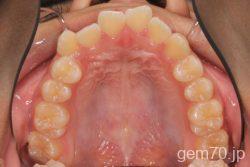

症状:開咬装置:セラミックブラケット | 抜歯世代:10代 | 高校生

主訴)前歯がかみ合わない

診断)開咬

年齢)18歳

使用装置)マルチブラケット装置

治療方法)抜歯 4|4/4|4

治療期間) 2年4ヵ月 通院回数 27回